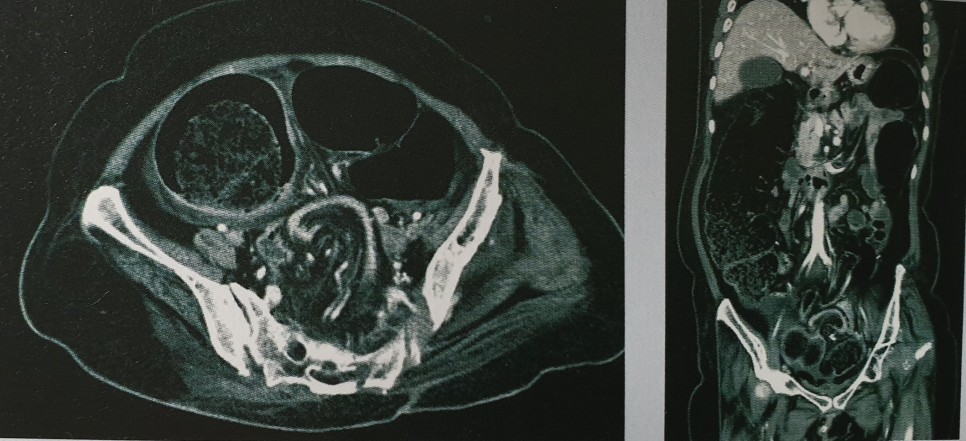

배 청진에서 장음은 증가하고 배는 팽만하고 배꼽 주위 압통이 있으면서 복부 CT 사진에서 mesentery의 whirling appearance를 보이므로 구불창자꼬임입니다. 그런데도 거짓장막힘을 골랐던 이유는 사진을 유심히 보지 않은 이유도 있지만 환자가 복통보다는 복부 팽만을 더 호소해서 그런 것이 아니었는지 하는 생각을 해 봅니다. 구불창자꼬임으로 내원하는 환자들은 주로 응급실로 내원하는 경우가 많고 복부 팽만도 있지만 수반되는 심한 복통을 주로 호소합니다.

위 CT 사진의 가운데를 보면 mesentery가 회전형으로 돌아가 보이는 부분이 있습니다. Central whirl sign이며 이것은 막힌 부위 양쪽의 afferent, efferent loop이 회전되어 생기며 mesentery가 꼬이게 된 것을 의미합니다. 건강했던 젊은 사람이라도 mechanical obstruction이 의심되는 경우에는 감별질환으로 volvulus를 생각해야 합니다.